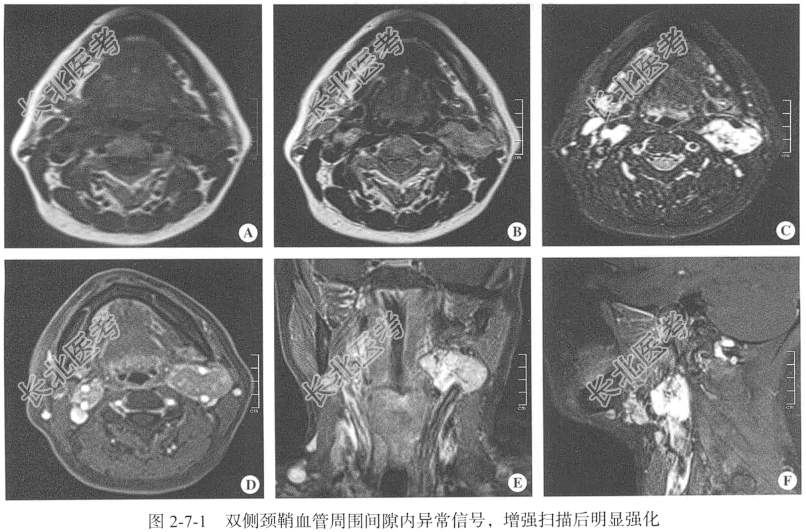

【影像图片】见图2-7-1。

【颈部MRI检查】仰卧位,横断位扫描,包括T₁WI、T₂WI及T₂脂肪抑制序列,扫描范围:寰椎至第5颈椎椎体间,扫描层厚为3.0mm;辅以矢状位T₂WI、冠状位T₂脂肪抑制序列平扫后行横断位、冠状位及矢状位增强扫描。

【手术所见】因双侧同时手术风险极大,建议先行较大的左侧肿物切除术,待术后恢复再行对侧手术。左侧肿物切除术发现左侧颈总动脉分叉处肿物,瘤体大小约为5.0cm×4.0cm,实性,血供丰富,伴有搏动,挤压后缩小,放松后立即恢复,分叉处已被瘤体包绕,瘤体上方少许组织较软,余组织及基底部较硬,考虑混合型;右侧肿物切除术从颈总动脉下方分叉处游离,发现分叉处3.0cm瘤体,瘤体紧贴颈内动脉及颈外动脉,瘤体与颈内动脉、颈外动脉粘连致密,瘤体上方少许组织较软,余组织及基底部较硬,考虑为混合型。

【病理诊断】颈动脉体瘤。